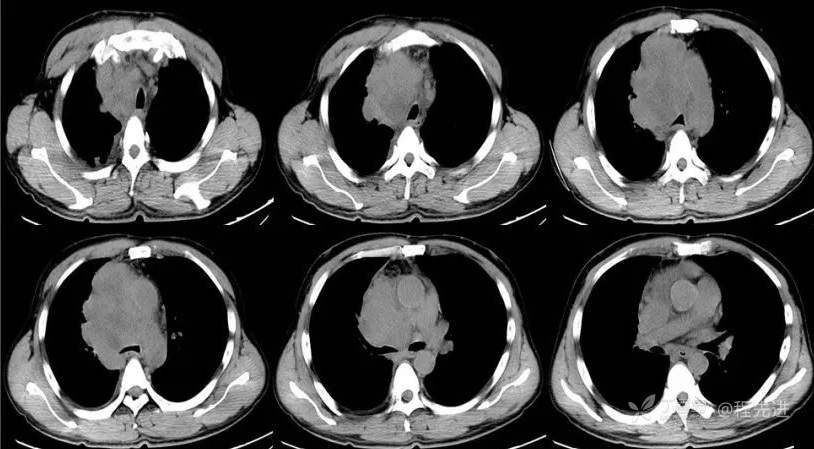

CT

平扫CT值约38HU,动脉期CT值约46HU,静脉期CT值约58HU